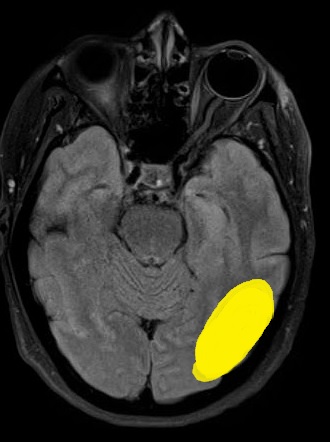

How do you localize a pie in the sky visual field defect? Well, the visual field defect affects both eyes, which tells you that it is behind the optic chiasm. Remember also that visual input is processed in the contralateral hemisphere, so a right sided visual defect localizes to the left hemisphere. Lastly, visual processing is inverted on the vertical (superior-inferior) axis.

A right homonymous superior quadrantopia localizes to a left temporal or occipital lobe lesion. Recall that the optic radiations pass through both the posterior temporal and parietal lobes.